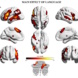

Es zeigte sich: Die Vierjährigen schnitten in beiden Aufgaben deutlich besser ab als die Dreijährigen, so wie es bereits frühere Studien gezeigt hatten. Anhand von MRT-Untersuchungen stellte sich zudem heraus, im Alter zwischen drei und vier Jahren reift das sogenannte kognitive Kontrollnetzwerk heran. Die Großhirnrinde, der Cortex, wird dicker.

Dieses Netzwerk bestimmt bei Erwachsenen darüber, wie gut wir in der Lage sind, unsere Impulse und Handlungen zu kontrollieren. Im ausgereiften Zustand umfasst es vor allem Regionen im Frontal- und Parietallappen des Gehirns, die wiederum durch Nervenfasern miteinander verbunden sind und so Informationen schnell und effizient austauschen können.

Das Interessante dabei: Die unterschiedlichen Aufgaben zur Selbstkontrolle, der „Bär-Drache“- und der Marshmallow-Test, standen mit unterschiedlichen Regionen innerhalb des kognitiven Kontrollnetzwerks in Verbindung.

Schnitten Kinder in ersterem gut ab, war der präfrontale Cortex weiter ausgebildet, der bei Erwachsenen insbesondere für die Planung und Steuerung von Handlungen zuständig ist.

Machten sich die Kleinen besser im Marshmallow-Test, war der supramarginale Gyrus im Reifeprozess stärker vorangeschritten, der eher mit der Steuerung von Aufmerksamkeit verbunden ist.